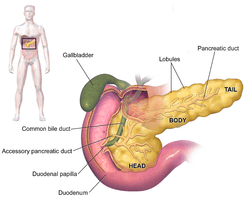

The symptoms of pancreatic adenocarcinoma do not usually appear in the disease's early stages, and are individually not distinctive to the disease.[5][6][28] The symptoms at diagnosis vary according to the location of the cancer in the pancreas, which anatomists divide (from left to right on most diagrams) into the thick head, the neck, and the tapering body, ending in the tail.

Regardless of a tumour's location, the most common symptom is unexplained weight loss, which may be considerable. A large minority (between 35% and 47%) of people diagnosed with the disease will have had nausea, vomiting or a feeling of weakness. Tumors in the head of the pancreas typically also cause jaundice, pain, loss of appetite, dark urine, and light-colored stools. Tumors in the body and tail typically also cause pain.[28]

For cancers involving the head of the pancreas, the Whipple procedure is the most commonly attempted curative surgical treatment. This is a major operation which involves removing the pancreatic head and the curve of the duodenum together ("pancreato-duodenectomy"), making a bypass for food from the stomach to the jejunum ("gastro-jejunostomy") and attaching a loop of jejunum to the cystic duct to drain bile ("cholecysto-jejunostomy"). It can be performed only if the person is likely to survive major surgery and if the cancer is localized without invading local structures or metastasizing. It can therefore be performed only in a minority of cases. Cancers of the tail of the pancreas can be resected using a procedure known as a distal pancreatectomy, which often also entails removal of the spleen.[4][6] Nowadays, this can often be done using minimally invasive surgery.[4][6]